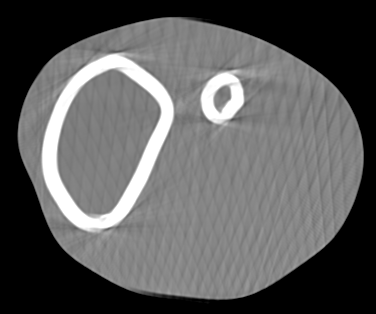

Involuntary subject motion is the main source of artifacts in weight-bearing cone-beam CT of the knee. To achieve image quality for clinical diagnosis, the motion needs to be compensated. We propose to use inertial measurement units (IMUs) attached to the leg for motion estimation. We perform a simulation study using real motion recorded with an optical tracking system. Three IMU-based correction approaches are evaluated, namely rigid motion correction, non-rigid 2D projection deformation and non-rigid 3D dynamic reconstruction. We present an initialization process based on the system geometry. With an IMU noise simulation, we investigate the applicability of the proposed methods in real applications. All proposed IMU-based approaches correct motion at least as good as a state-of-the-art marker-based approach. The structural similarity index and the root mean squared error between motion-free and motion corrected volumes are improved by 24-35% and 78-85%, respectively, compared with the uncorrected case. The noise analysis shows that the noise levels of commercially available IMUs need to be improved by a factor of $10^5$ which is currently only achieved by specialized hardware not robust enough for the application. The presented study confirms the feasibility of this novel approach and defines improvements necessary for a real application.